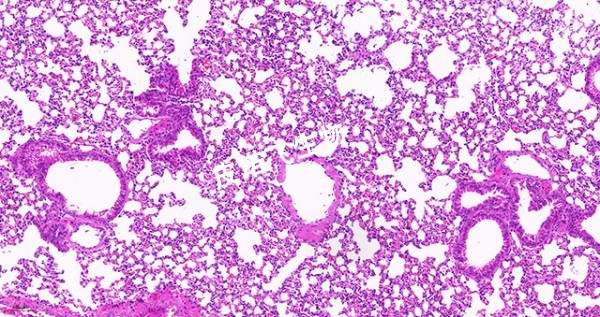

He染色